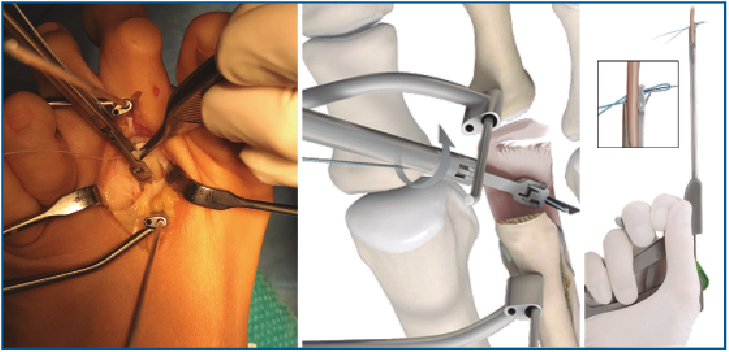

5. Pasamos las suturas por la placa plantar con ayuda de una pinza Mini-Scorpion DX® (Arthrex) (Figura 7) o de un Micro SutureLasso® (Arthrex) (Figura 8). Existen diferentes técnicas según el tipo de rotura. Para la reinserción utilizamos 2 suturas no reabsorbibles de Fiber-Wire® n.º 0 en “doble hilera” proximal y distal (Figura 9). Decidimos una u otra configuración in situ según el tipo de rotura.

Figura 7. Pase de suturas mediante pinza Mini-Scorpion®.

Figura 8. Pase de suturas con ayuda de Micro SutureLasso®.

6. Retiramos el distractor y la agK de la falange, y realizamos 2 pequeños túneles de dorsal a plantar en la base de F1 con una broca o agK de 1,2 mm (Figura 10). Estos pueden disponerse cruzados o en paralelo. Aunque la disposición paralela pudiera teóricamente debilitar la base de F1 al ser prácticamente subcondrales, realizarlos cruzados tiene la desventaja de poder interferirse en el pase de las suturas. A través de estos túneles recuperamos las suturas preparadas en el extremo distal de la placa, de plantar a dorsal (Figura 11 y Vídeo).